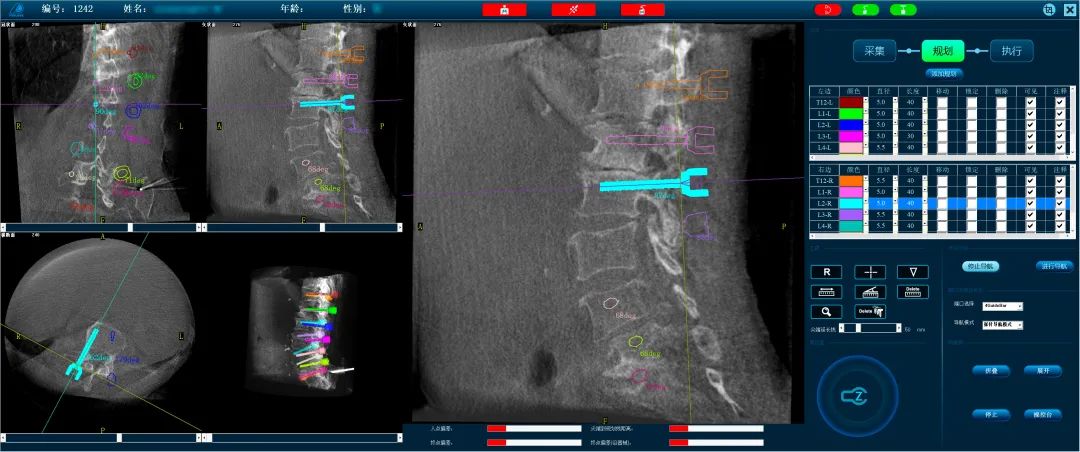

Precise Planning of 14 Screws in One Go Utilizing the Perlove Medical 3D C-arm system, intraoperative three-dimensional images were obtained and transmitted to the orthopedic surgical robot workstation. Using surgical planning software, the surgeon precisely planned the positioning of 14 screws in a single session. Images: [Insert images] Compared to traditional surgery, where screw positioning requires multiple manual entries, this robot-assisted system significantly saved planning and positioning time, simplifying the surgical steps and enhancing screw placement efficiency.